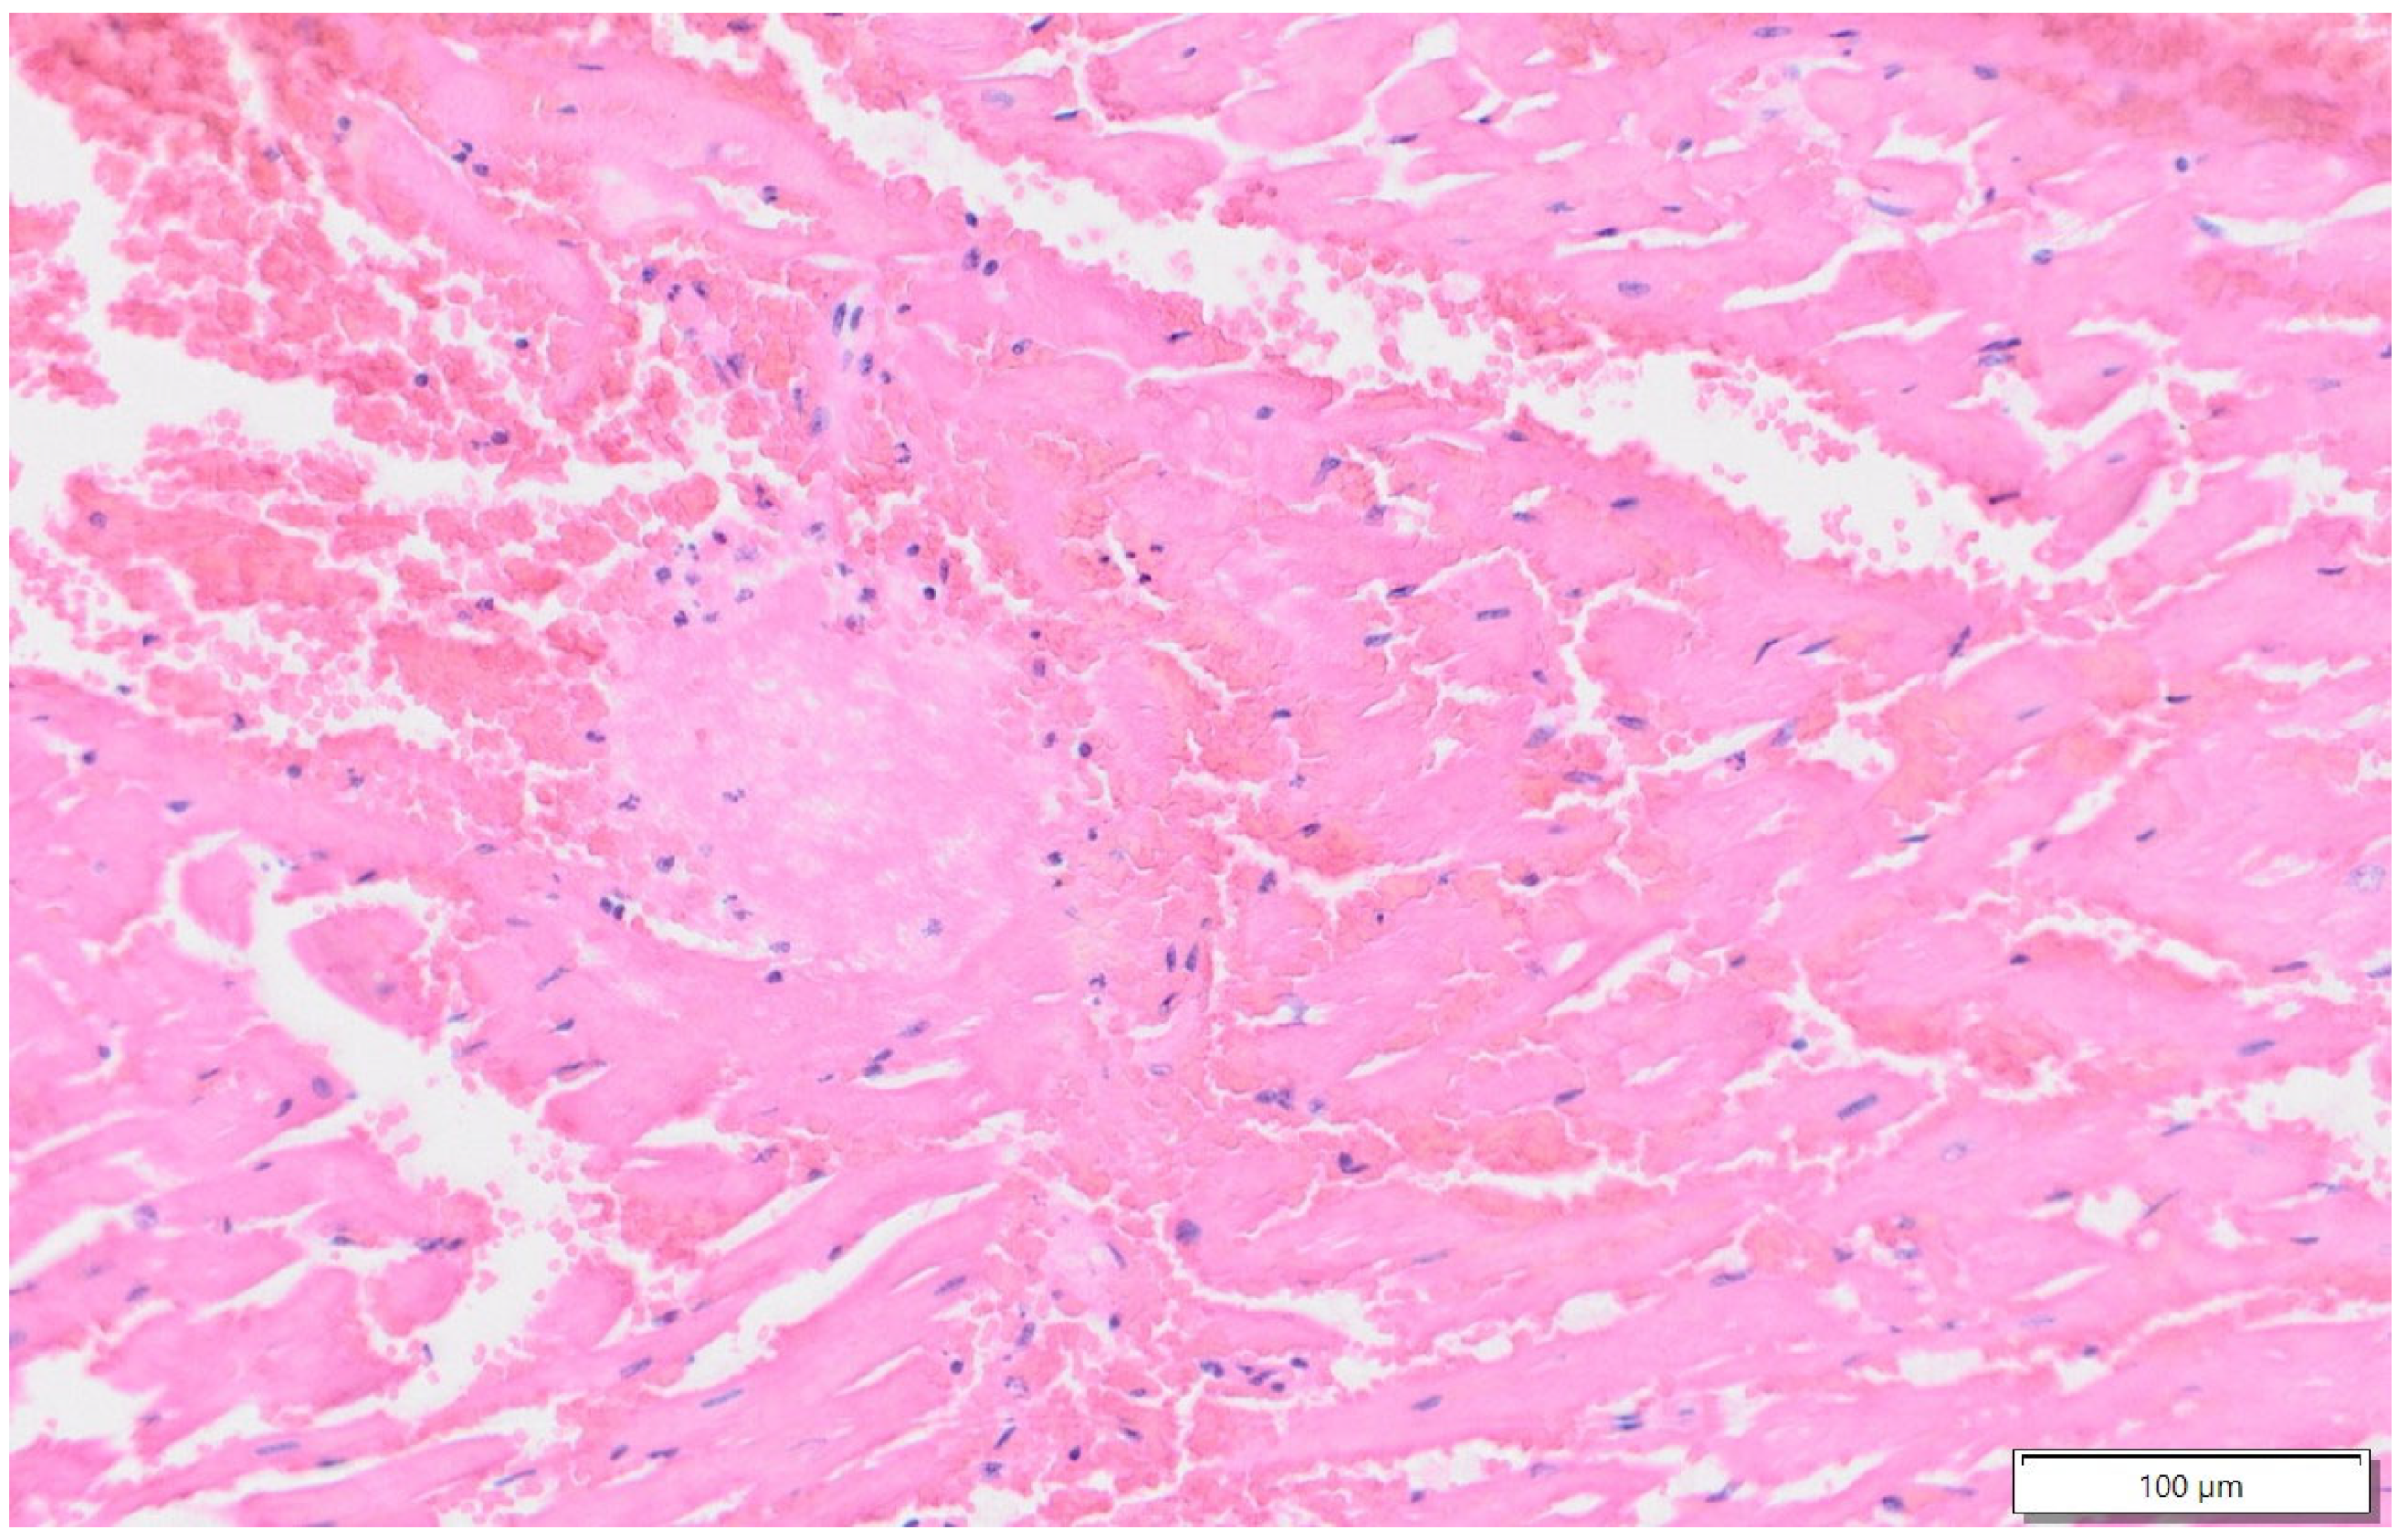

2.1. Case 1

2.2. Case 2

2.3. Case 3

3. Discussion